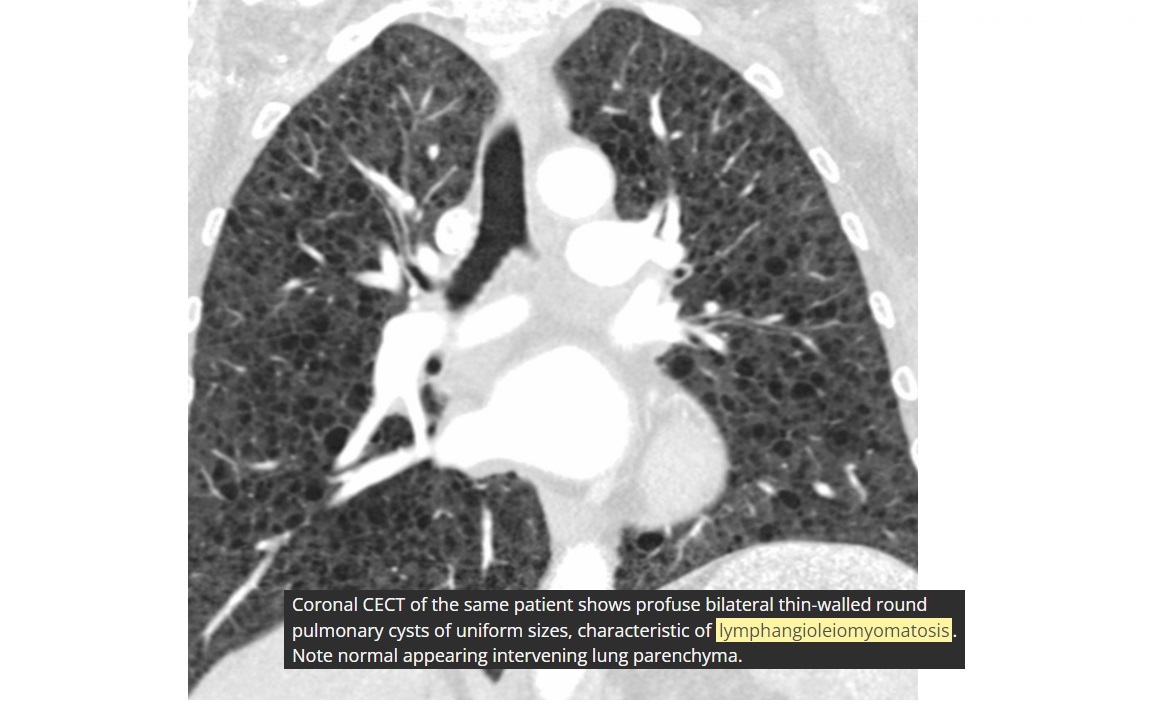

Lymphangioleiomyomatosis (LAM)

Diffuse no lobe predominant Thin walled cysts

Spontaneous PTX

Premenopausal women

NORMAL lung volumes

Chylous pleural effusions

increased lung volumes

Associated with tuberous sclerosis - 1/3rd have AMLs